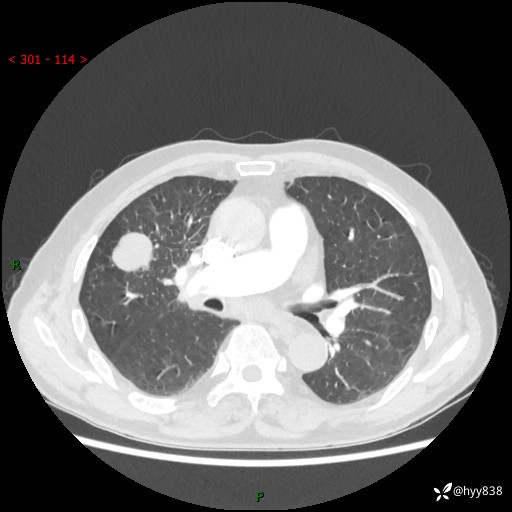

69岁/男,间断咳嗽伴气促、下肢水肿。临床拟诊肺栓,偶发肺均质强化结节--结果公布

【患者信息】:69岁/男

【主诉】:间断咳嗽伴气促、下肢水肿2周

【现病史及既往史】:患者2周来无明显诱因出现咳嗽,咳少量白痰,不易咳出,伴有气促,呈间断发作,症状与活动费力相关,以夜间为甚,不能平躺入睡,偶有憋醒,无胸闷胸痛、无发热、无头晕、头痛等不适,伴有双下肢中度水肿,就诊于当地县人民医院门诊,完善相关检查提示:左下肢深静脉血栓形成,未予以特殊处理,今患者为求进一步诊治来我院就诊,拟“心衰”收入我科。 起病以来,患者精神、饮食、睡眠可,大小便如常,体力明显下降,体重未见明显减轻。

【检查】:胸部CT增强